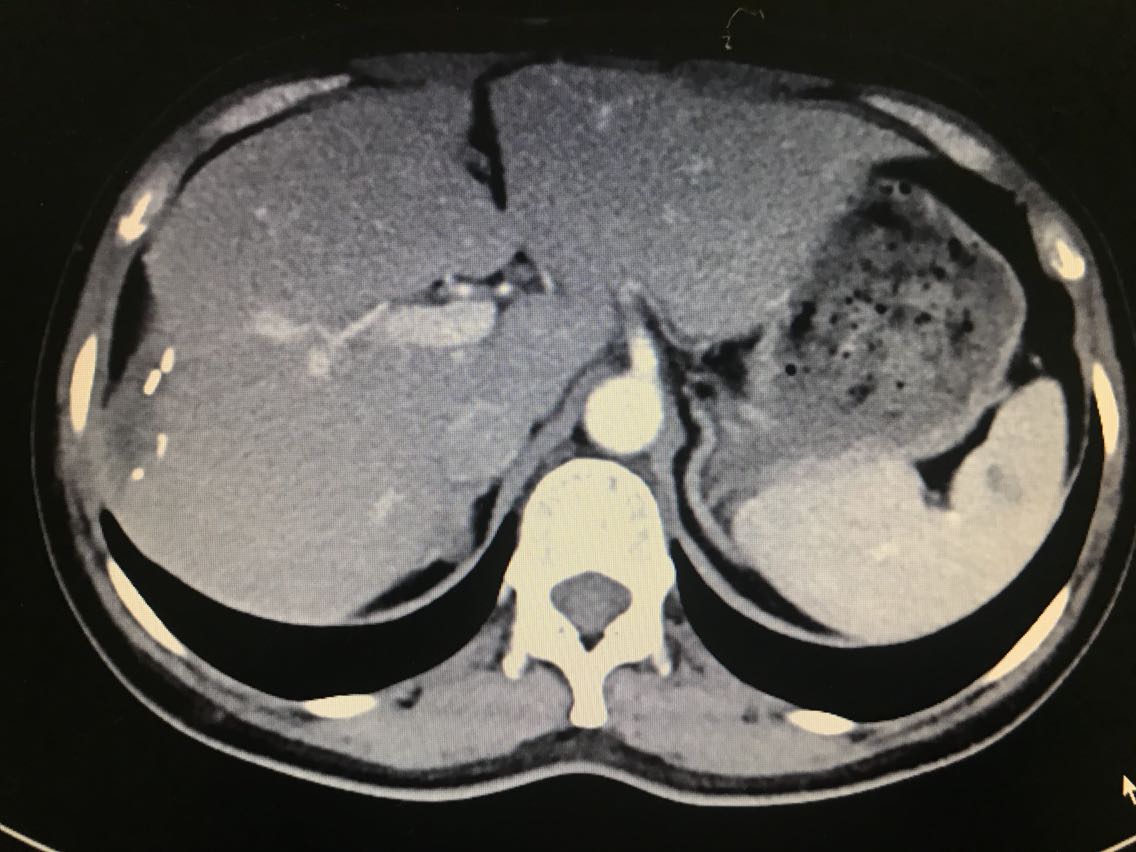

查体无特殊。 辅助检查: 全腹CT:右侧肾上腺占位。

诊断:1.原发性醛固酮增多症(右侧优势侧)2.右侧肾上腺结节 治疗:腹腔镜右肾上腺肿瘤切除术 术中见:右侧肾上腺肿物与肾周紧密粘连,金黄色,约1.0*1.8*1.0cm大小。剖视肿瘤为鱼肉状实性肿物。